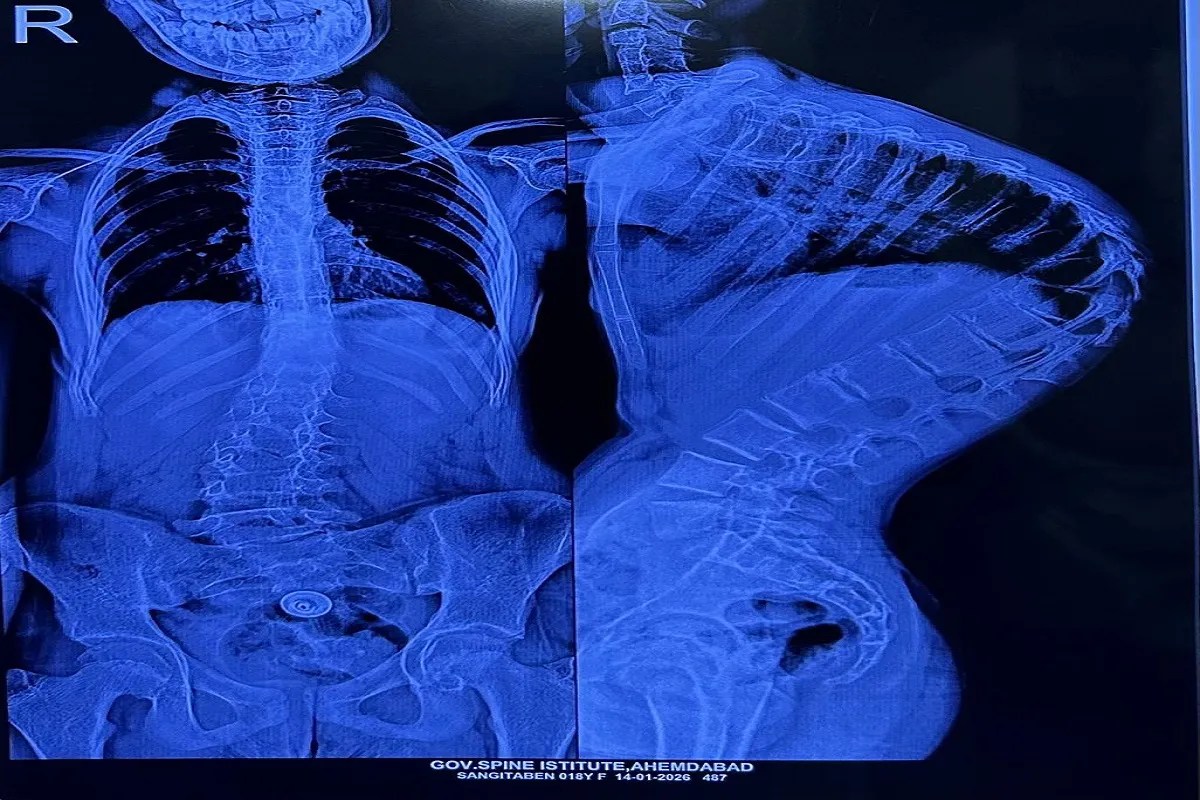

सर्जरी के बाद और पहले।

Ahmedabad. सिविल मेडिसिटी के गवर्नमेंट स्पाइन इंस्टीट्यूट ने एक बार फिर चिकित्सा नवाचार और मानवीय सेवा का अद्भुत उदाहरण पेश किया है। यहां आयोजित दूसरे इंडो-अमेरिकन स्पाइन सर्जरी कैंप में सात बच्चों की जटिल काइफोस्कोलियोसिस सर्जरी सफलतापूर्वक की गई। इन बच्चों की रीढ़ की हड्डी सांप की तरह टेढ़ी-मेढ़ी हो चुकी थी, जिससे उनका जीवन कठिनाई और खतरे से भरा था।गवर्नमेंट स्पाइन इंस्टीट्यूट के निदेशक डॉ. पियुष मित्तल ने बताया कि इस तरह की सर्जरी का खर्च निजी अस्पतालों में 5 से 10 लाख रुपए तक होता है, लेकिन सरकारी सहयोग से यह उपचार पूरी तरह नि:शुल्क किया गया। इस पहल से न केवल गुजरात बल्कि अन्य राज्यों से आए बच्चों को भी नई उम्मीद मिली है।

डॉ. मित्तल के अनुसार यह अत्यंत जोखिमपूर्ण ऑपरेशन होता है। 4 से 5 घंटे तक चलने वाली इस प्रक्रिया में रीढ़ की हड्डी को सीधा करते समय नसों और रक्तवाहिनियों के बीच बेहद सावधानी से काम करना पड़ता है। थोड़ी चूक भी मरीज को जीवनभर का लकवाग्रस्त कर सकती है। इस जोखिम को कम करने के लिए अमेरिकी न्यूरो-मॉनिटरिंग टीम और एनेस्थीसिया विशेषज्ञों ने अहम भूमिका निभाई। सर्जरी के बाद बच्चों के लिए पोस्ट-ऑपरेटिव रिहैबिलिटेशन पर भी खास ध्यान दिया जा रहा है। इस सफल प्रयोग ने साबित किया है कि उच्च तकनीक और विशेषज्ञ हाथ मिलकर आम लोगों के जीवन में बड़ा बदलाव ला सकते हैं।